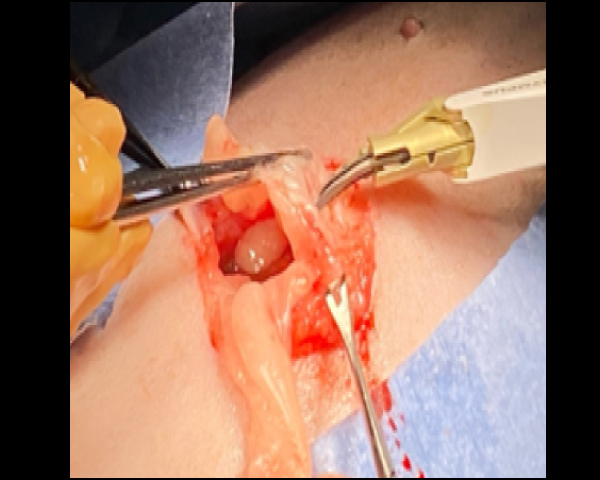

リトラクターリングを用いてアポクリン腺癌の摘出